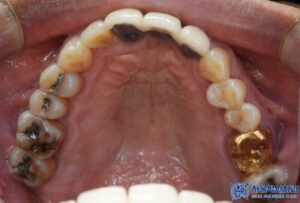

위 환자분께서는 오랫동안 없던 어금니뿐만 아니라

나머지 불편한 치아들도 함께 치료를 원하셨는데요.

또한, 다른 치아들의 충치와 손상된 부위에 대해서도

신경치료와 보철 치료를 함께 진행하며,

전반적인 구강 건강을

회복할 수 있도록 도와드리기로 하였습니다.

임플란트 치료 외에도, 환자분의 남아있는

치아들 중 심한 충치가 있는 어금니

(오른쪽 위 큰 어금니, 왼쪽 위 작은 어금니,

왼쪽 위 큰 어금니, 왼쪽 아래 큰 어금니)는

신경치료를 진행하였습니다.